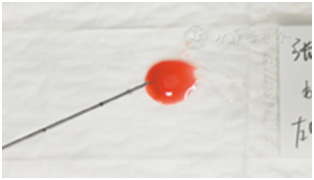

遇标本内血液成分较多时(图26),可以采取以下措施减轻红细胞对镜下观察标本效果的干扰。①将标本分散至数张载玻片,避免单张涂片标本过厚,削弱红细胞对其它细胞的覆盖程度。②穿刺操作时,根据具体情况在抽吸法和非抽吸法之间灵活转换应用。抽吸法穿刺获得标本含血液较多时,可以改为非抽吸法再次穿刺;非抽吸法穿刺获得标本含量较少时,可以改为抽吸法再次穿刺。③采用TCT细胞采集技术,消除红细胞的影响,提高甲状腺结节细胞的观察效果。

图26标本中血液成分过多 A:肉眼观标本量充足,但是以血液为主;B:光镜下见红细胞过多(×10)

当不具备现场快速细胞学评估条件时,通过培训非细胞学医生对置于载玻片上的标本或液基保存液中的标本进行现场裸眼评估的技能,具有较高的可行性和一定的实际效果。现场观察发现标本稠厚,意味着标本中细胞数量更多、更充分,显微镜下的细胞学诊断效能更高(图27)。反之,标本稀薄则提示细胞量可能不足,影响细胞学诊断效能(图28)。标本中颗粒物丰富者,意味着镜下细胞量较多,易获得有效诊断,得到阳性结果的比例也更高(图29);颗粒物较少甚或无颗粒物者则反之。尽管现场裸眼评估不能代替镜下分析,但通过评估可合理调整穿刺针数,增强操作者穿刺成功的信心[31]。

图27标本稠厚,且颗粒物丰富 A:肉眼观标本量充足,肿瘤组织颗粒较多,血液成分较少;B:光镜下见肿瘤细胞多,红细胞较少(×10)